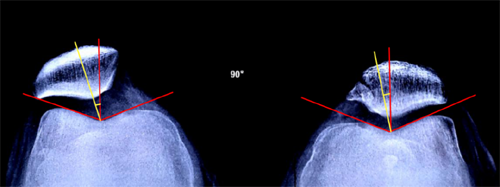

儿童青少年髌骨脱位也是常见病,脱位表现形式多样,包括先天性,习惯性,复发性,急性脱位,专业组选择特别针对生长期儿童设计的手术方式,稳定复位髌骨同时不损伤生长潜力,目前有较大规模患者微信群2个,一直进行长期跟踪随访。